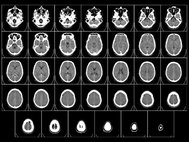

Поэтому авторы решили проверить, что произойдет, если удвоить только ген SHANK3. Для этого они создали соответствующих трансгенных мышей. Трансгенные мыши вели себя гиперактивно, сидя в клетке, а будучи выпущены на свободу, быстрее и больше бегали. Поскольку у одного из пациентов с дупликацией наблюдался СДВГ, авторы решили проверить, нет ли здесь прямой причинно-следственной связи. Они стали давать мышам лекарство против СДВГ - вещество ряда амфетамина, но оно не помогло.

Параллельно с этим авторы исследования искали людей, с удвоением небольшого участка, не затрагивающим других генов, кроме SHANK3. И они нашли. Это оказалась девочка 11 лет с диагнозом СДВГ, которой, как и мышам, не помогала стандартная терапия, и 35-летний мужчина с маниакально-депрессивным психозом и эпилепсией. Тут надо оговориться, что психиатрические диагнозы, особенно у детей, часто бывают условны. Клиническая картина часто размыта и подходит под несколько диагнозов. Действительно, и поведение мышей, и обоих пациентов с дупликацией маленького участка 22-й хромосомы вполне похоже на маниакальные проявления маниакально-депрессивного психоза, сопровождающиеся припадками. Обнаружив это, авторы дали мышам вальпроевую кислоту – антиконвульсант и нормотимик, стабилизирубщий настроение. Вальпроевая кислота сумела победить симптомы, вызванные дополнительной копией гена SHANK3.